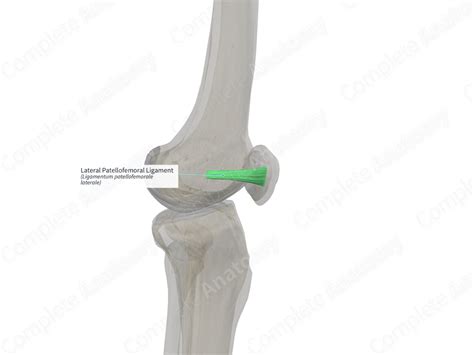

The MPFL works in conjunction with other structures, including the vastus medialis obliquus (VMO) muscle, the lateral patellofemoral ligament, and the medial patellotibial ligament, to provide comprehensive stability to the patella. The VMO, in particular, plays a significant role in dynamic stabilization by contracting to pull the patella medially during knee extension.